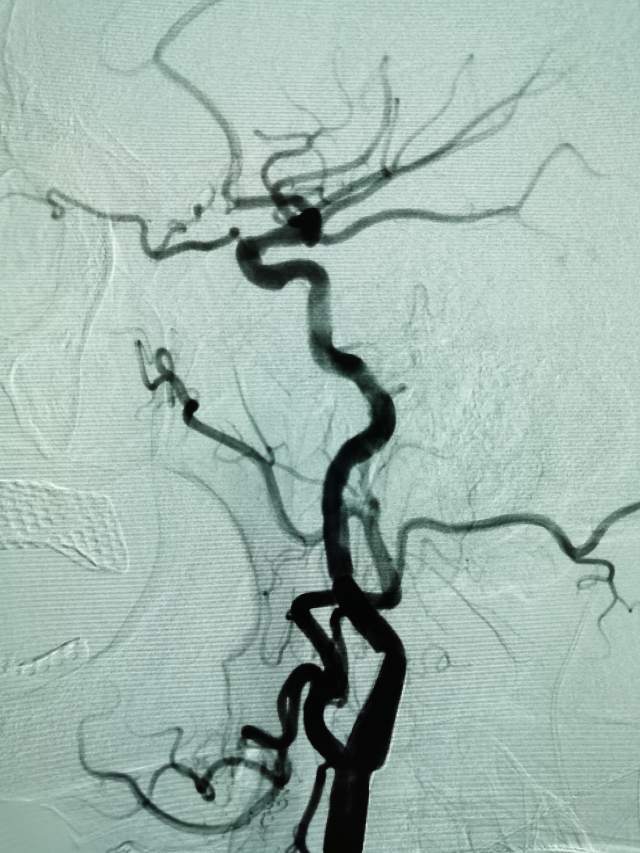

进一步行DSA检查后发现:左侧颈内动脉起始部有一个颈动脉蹼。这个血管内的“蹼”,是一个薄片状的结构,类似掌部的“蹼”,它会在颈内动脉起始部产生“扰流效应”,瘀滞的血流存在栓子形成和脱落的风险………,冲散的栓子可以“天女散花”,也可以“天上掉下石头”,这不,这位兄弟就被掉下的石头砸到颅内的功能区了,手脚语言都砸坏了。